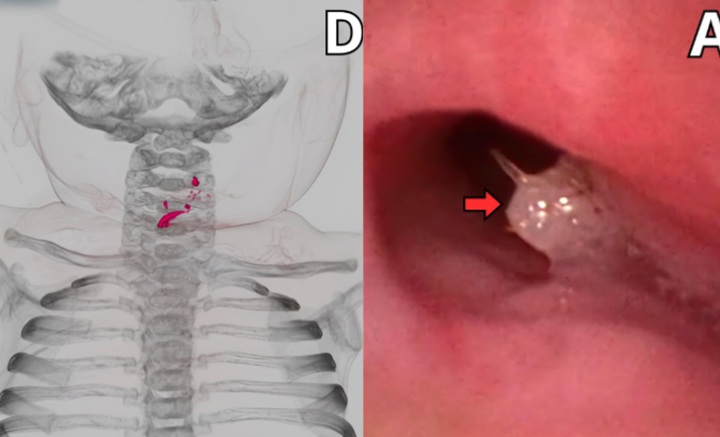

상급병원에서 검사한 결과, 기관지에 물고기로 추정되는 백색 이물질이 있었고 식도에 가시 2개가 박혀 있었다. 이 밖에 물고기 가시, 비늘로 추정되는 여러 개의 이물질이 있었고 이로 인해 식도가 찢어지고 구멍이 난 상태였다.

의료진은 기관내 튜브와 집게, 식도위십이지장내시경 등으로 생선 가시, 비늘 등을 제거하는 치료를 시행했다. 다행히 시술 후 아기는 입원 19일째에 중환자실에서 일반실로 옮겨졌고, 25일째에는 일반식을 섭취할 수 있게 돼 퇴원했다. 이후 추적 검사에서도 합병증 없이 건강하게 회복된 것으로 확인됐다.